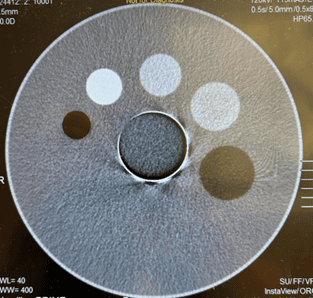

L’image ci-dessous montre l’artefact initial rencontré par le client.

La carte QV-ADC15 a été remplacée et un ensemble complet d’étalonnages NRA et Air a été effectué. Vous trouverez ci-dessous le scan d’assurance qualité final du fantôme TOS montrant que tous les artefacts en anneau ont été résolus et la fin d’une réparation réussie.